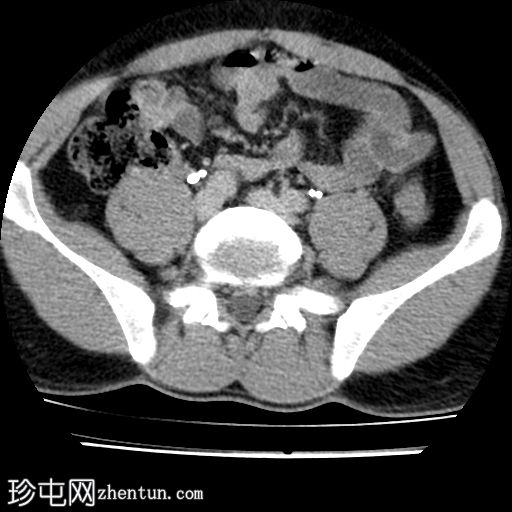

轴位

非增强

2.jpg